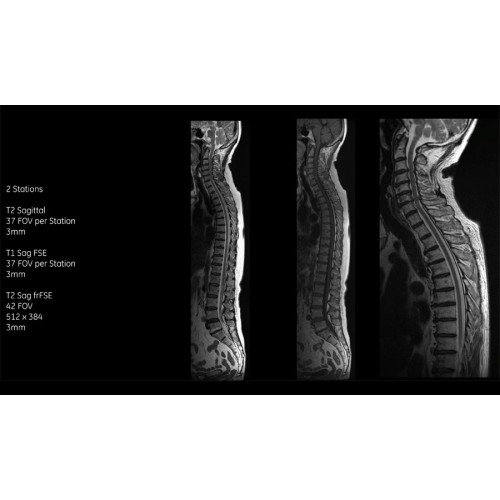

• Технология Digital Surround Technology (DST) — это новая технология объемной оцифровки данных, объединяющая сигналы от каждого элемента катушки. Прекрасное соотношение сигнал/шум и чувствительность поверхностных катушек в сочетании с превосходной однородностью и высокой проникающей способностью встроенной радиочастотной катушки — все это позволяет создавать качественные изображения не только позвоночника, но и всего тела.

Технологии SIGNA Pioneer позволяют проводить полное исследование брюшной полости при свободном дыхании, минимизируя артефакты движения пациента, в том числе с МР-динамическим контрастированием.